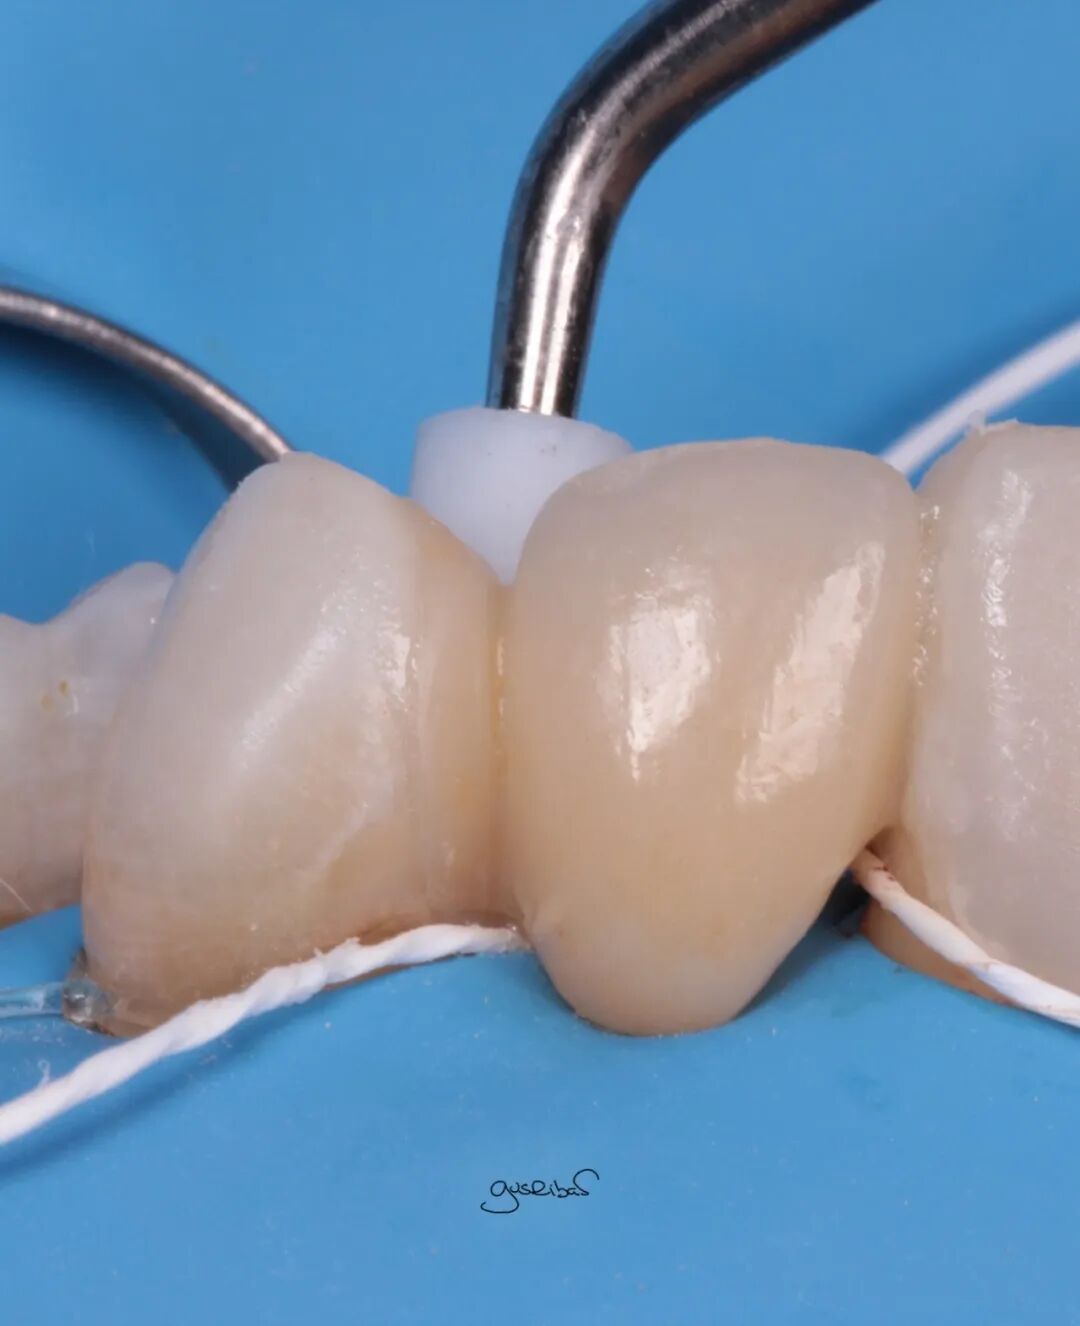

我使用粘接剂和复合树脂密封了根管,力求使其尽可能光滑和适应,